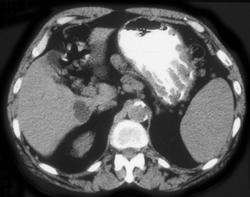

Menetrier's Disease